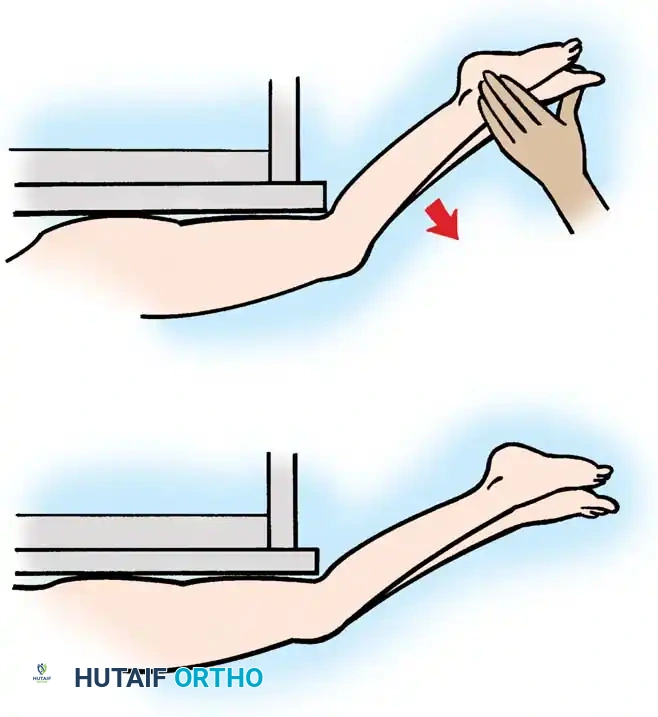

Quadriceps and Rectus Femoris Assessment

Quadriceps strength is best assessed with the patient supine and the lower legs dangling off the end of the examination table. The examiner extends the hips, allows the knees to flex passively, and then instructs the patient to voluntarily extend the knees against manual resistance.

Fig. 30-23 Testing for quadriceps strength. A, With hips extended, knees are allowed to flex off end of table. B, Patient voluntarily extends knees from flexed position against resistance.